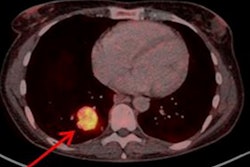

SSTRs are overexpressed on a wide range of NET cells. PET imaging of abnormal SSTR activity has largely replaced scintigraphic imaging using indium-111 pentetreotide (OctreoScan), and this change has been driven by the development of a new generation of radiotracers, the authors wrote.

Specifically, SSTR PET imaging with gallium-68 (Ga-68) DOTATATE, Ga-68 DOTATOC, and copper-64 (Cu-64) DOTATATE can improve the sensitivity of lesion detection, lower radiation dose, and provide shorter and more convenient study durations. The new guideline focuses on these PET radiotracers.